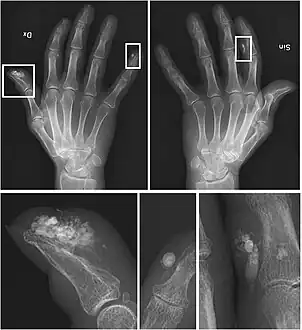

CREST syndrome (calcinosis and sclerodactyly)

CREST causes thickening and tightening of the skin with deposition of calcific nodules ("calcinosis").

Sclerodactyly

Though it is the most easily recognizable manifestation, it is not prominent in all patients. Thickening generally only involves the skin of the fingers distal to the metacarpophalangeal joints in CREST. Early in the course of the disease, the skin may appear edematous and inflamed. Eventually, dermal fibroblasts overproduce extracellular matrix leading to increased tissue collagen deposition in the skin. Collagen cross-linking then causes a progressive skin tightening. Digital ischemic ulcers commonly form on the distal fingers in 30–50% of patients.[3]